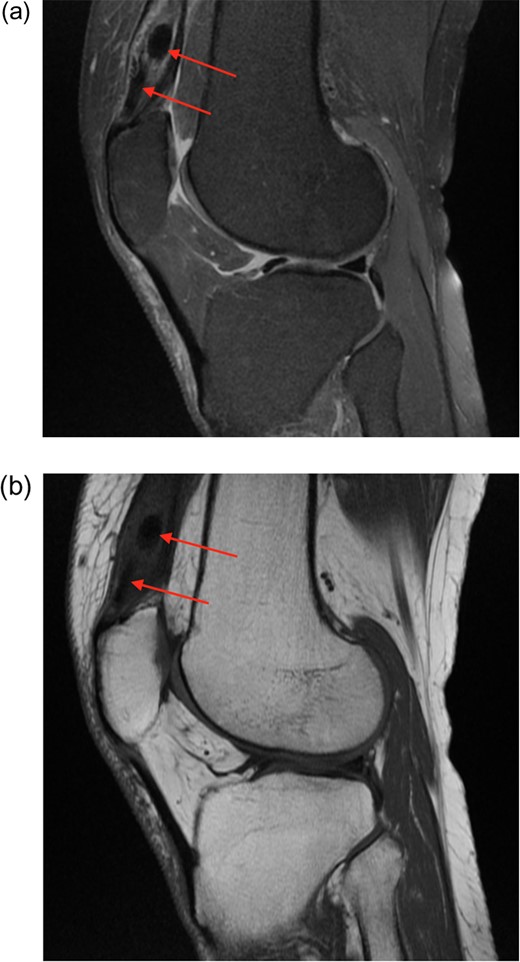

Plain radiographs and an MRI scan of the left knee were undertaken.

Radiographic appearance and MRI signal change confirmed calcification rather than ossification or enthesopathy. An unusual diagnosis of dystrophic calcification of the left quadriceps tendon was made (Figs 1–4).

(a) Proton density fat saturated (PDfs) sagittal MRI. There is enlargement of the distal quadriceps tendon, with splayed fibres separated by solid low signal foci. (b) T1 sequence MRI also showing low signal lesions.